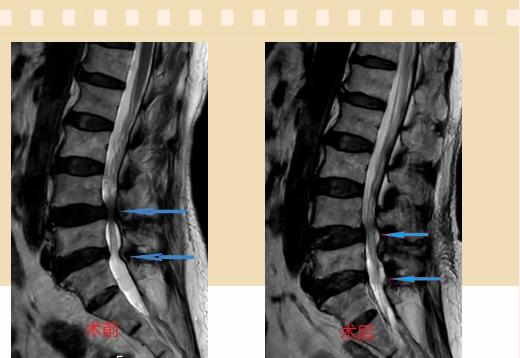

入院后李鵬副主任醫師為其進行了詳細的查體,完善了術前的檢查,明確診斷為:腰椎管狹窄癥(L4/5、L5/S1),病人合并2型糖尿病,請內分泌科會診,穩定血糖后,麻醉科會診病人,排除手術禁忌,李鵬為病人制定了手術方案:單側入路雙側減壓(ULBD)。

手術采用三個微創小切口,兩個節段減壓手術時間2.5小時,出血50ml。術后2天腰圍保護下床活動,術后5天順利出院。

傳統腰椎管狹窄癥的手術治療,往往需要切開減壓,同時需要內固定融合術,創傷很大,同時可能需要輸血,臥床時間較長,病人合并糖尿病,感染風險也高,而本次采用的UBE-ULBD手術切口更小(加起來約3cm,如果是單節段狹窄只需要不到2cm切口)、創傷更小,術后恢復較快,可以更早地恢復正常活動。

此外,手術保留了病變節段的穩定性,是一種微創的椎管減壓手術,能通過切除部分椎板、關節突關節、黃韌帶來解除神經根和硬膜囊的壓迫,不需要額外行腰椎內固定術,不需要螺釘及融合器的植入,病人術后腰椎的活動度不受影響。(盧   闖  劉   旭   袁錦鈺)